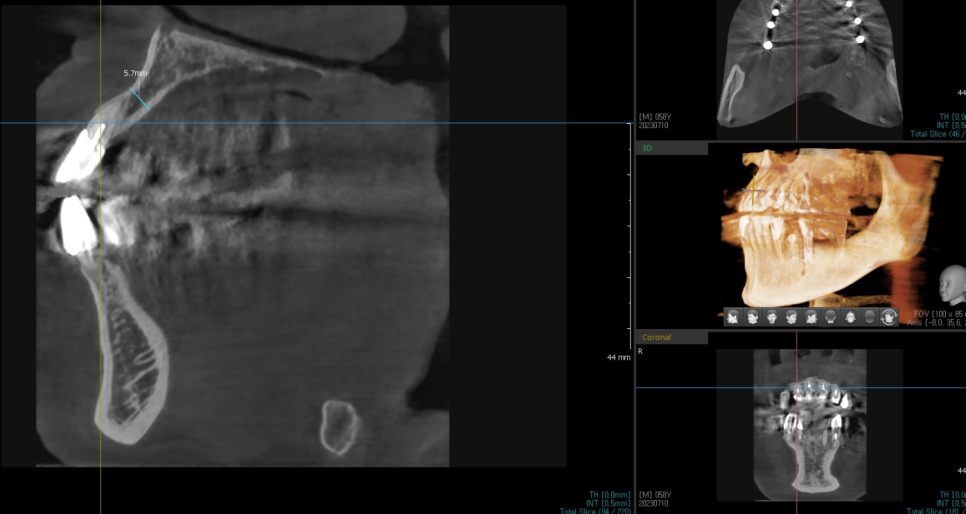

상일동역 치과에서 보유한 ct로 남아있는 잇몸 뼈부터 살펴보았습니다.

앞니는 잇몸 뼈가 가장 얇은 부위다 보니

뼈가 없어 임플란트가 어려울 수도 있거든요~

다행히 수술을 하는데 무리는 없어보였습니다.